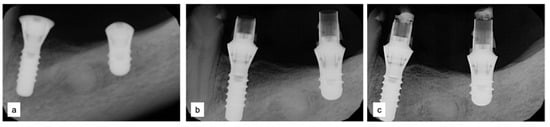

Two implants (Institute Straumann, Basel, Switzerland) of 4 × 12 mm and 5 × 8 mm were inserted in the 3.4 and 3.6 areas, respectively (Figure 9a). The final prosthesis was manufactured with a digital workflow and delivered after three months. The patient was monitored with clinical and radiographic evaluations 12 and 18 months after prosthetic loading. The clinical examination and the digital scans at 12 months of follow-up proved the efficacy of the regenerative approach (Figure 10 and Figure 11). The comparison between 12 (Figure 9b) and 18 month (Figure 9c) radiographs showed stability of the bone crest around the dental implants. Furthermore, a progressive mineralization of the regenerated area was also evident (Figure 9a–c).

Figure 9.

Periapical radiographs (a) immediately after implant placement (Institute Straumann, Basel, Switzerland), (b) after 12 months, and (c) after 18 months of prosthetic loading.